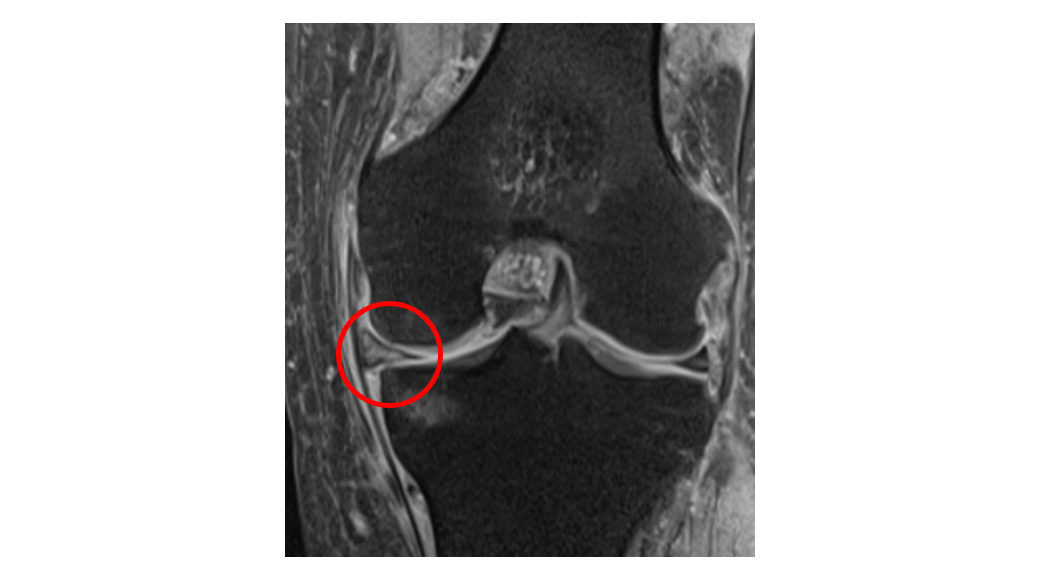

半月板損傷

MRI

軟骨・半月板・骨髄病変・滑膜まで評価でき、関節内の詳細な情報を得るのに有用です。